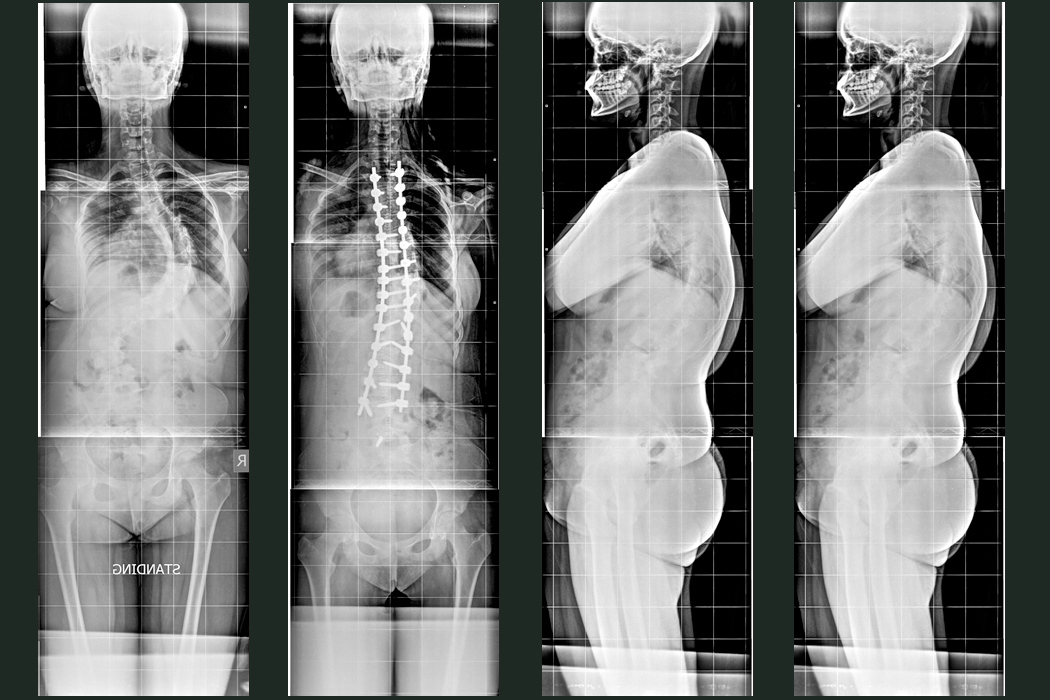

Patient B

A 12 year old school girl was presented with severe deformity of back for the last 2 years. She was initially managed with Halo application followed by Posterior Scoliosis correction done in the year 2021.

Hover over the image to view Pre & Post-op X-Rays